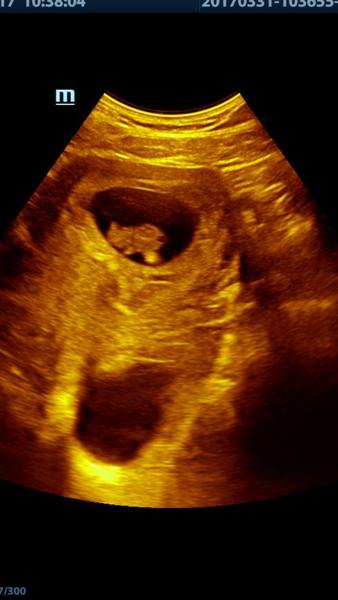

baby tak nasa mala rybka (na fotke zo sona tak vyzera :D ) ma uz 2,06cm srdiecko bije o stosest, termin sa posunul o dva dni neskor podla velkosti a tym padom presne viem kedy sme si zamiesili :D 13.2. o pol5 rano ked sa mi nedalo spat a zobudila som si chlapa, ze mam chut :D riadna nahoda, ze? 🙂